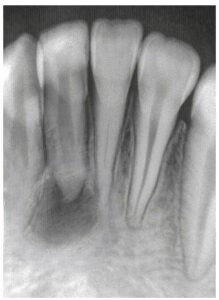

Lesión Endo-Perio Combinada

Una lesión endo-perio combinada es una condición en la que hay tanto una infección de la pulpa como una enfermedad periodontal.

Los pacientes pueden experimentar dolor, hinchazón y movilidad dental.

El tratamiento incluye tanto el tratamiento de conducto como el tratamiento periodontal para abordar ambas infecciones. La coordinación entre el endodoncista y el periodoncista es esencial.